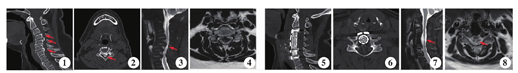

患者 女,68岁,间断性双上肢麻木感并疼痛1年余,体查双侧Hoffmann(+)。影像学检查提示C4至C6-7混合型OPLL(图1,图2),C4-5骨赘椎管占位率为61.3%,脊髓严重受压(图3,图4),JOA评分11.5分。行C4、C5双椎体ACCF加C6-7单节段ACDF手术治疗。术后1年随访时,复查影像学提示椎管减压彻底(图5,图6),脊髓压迫解除(图7,图8),JOA评分14分, Cobb角改善率45.5%。